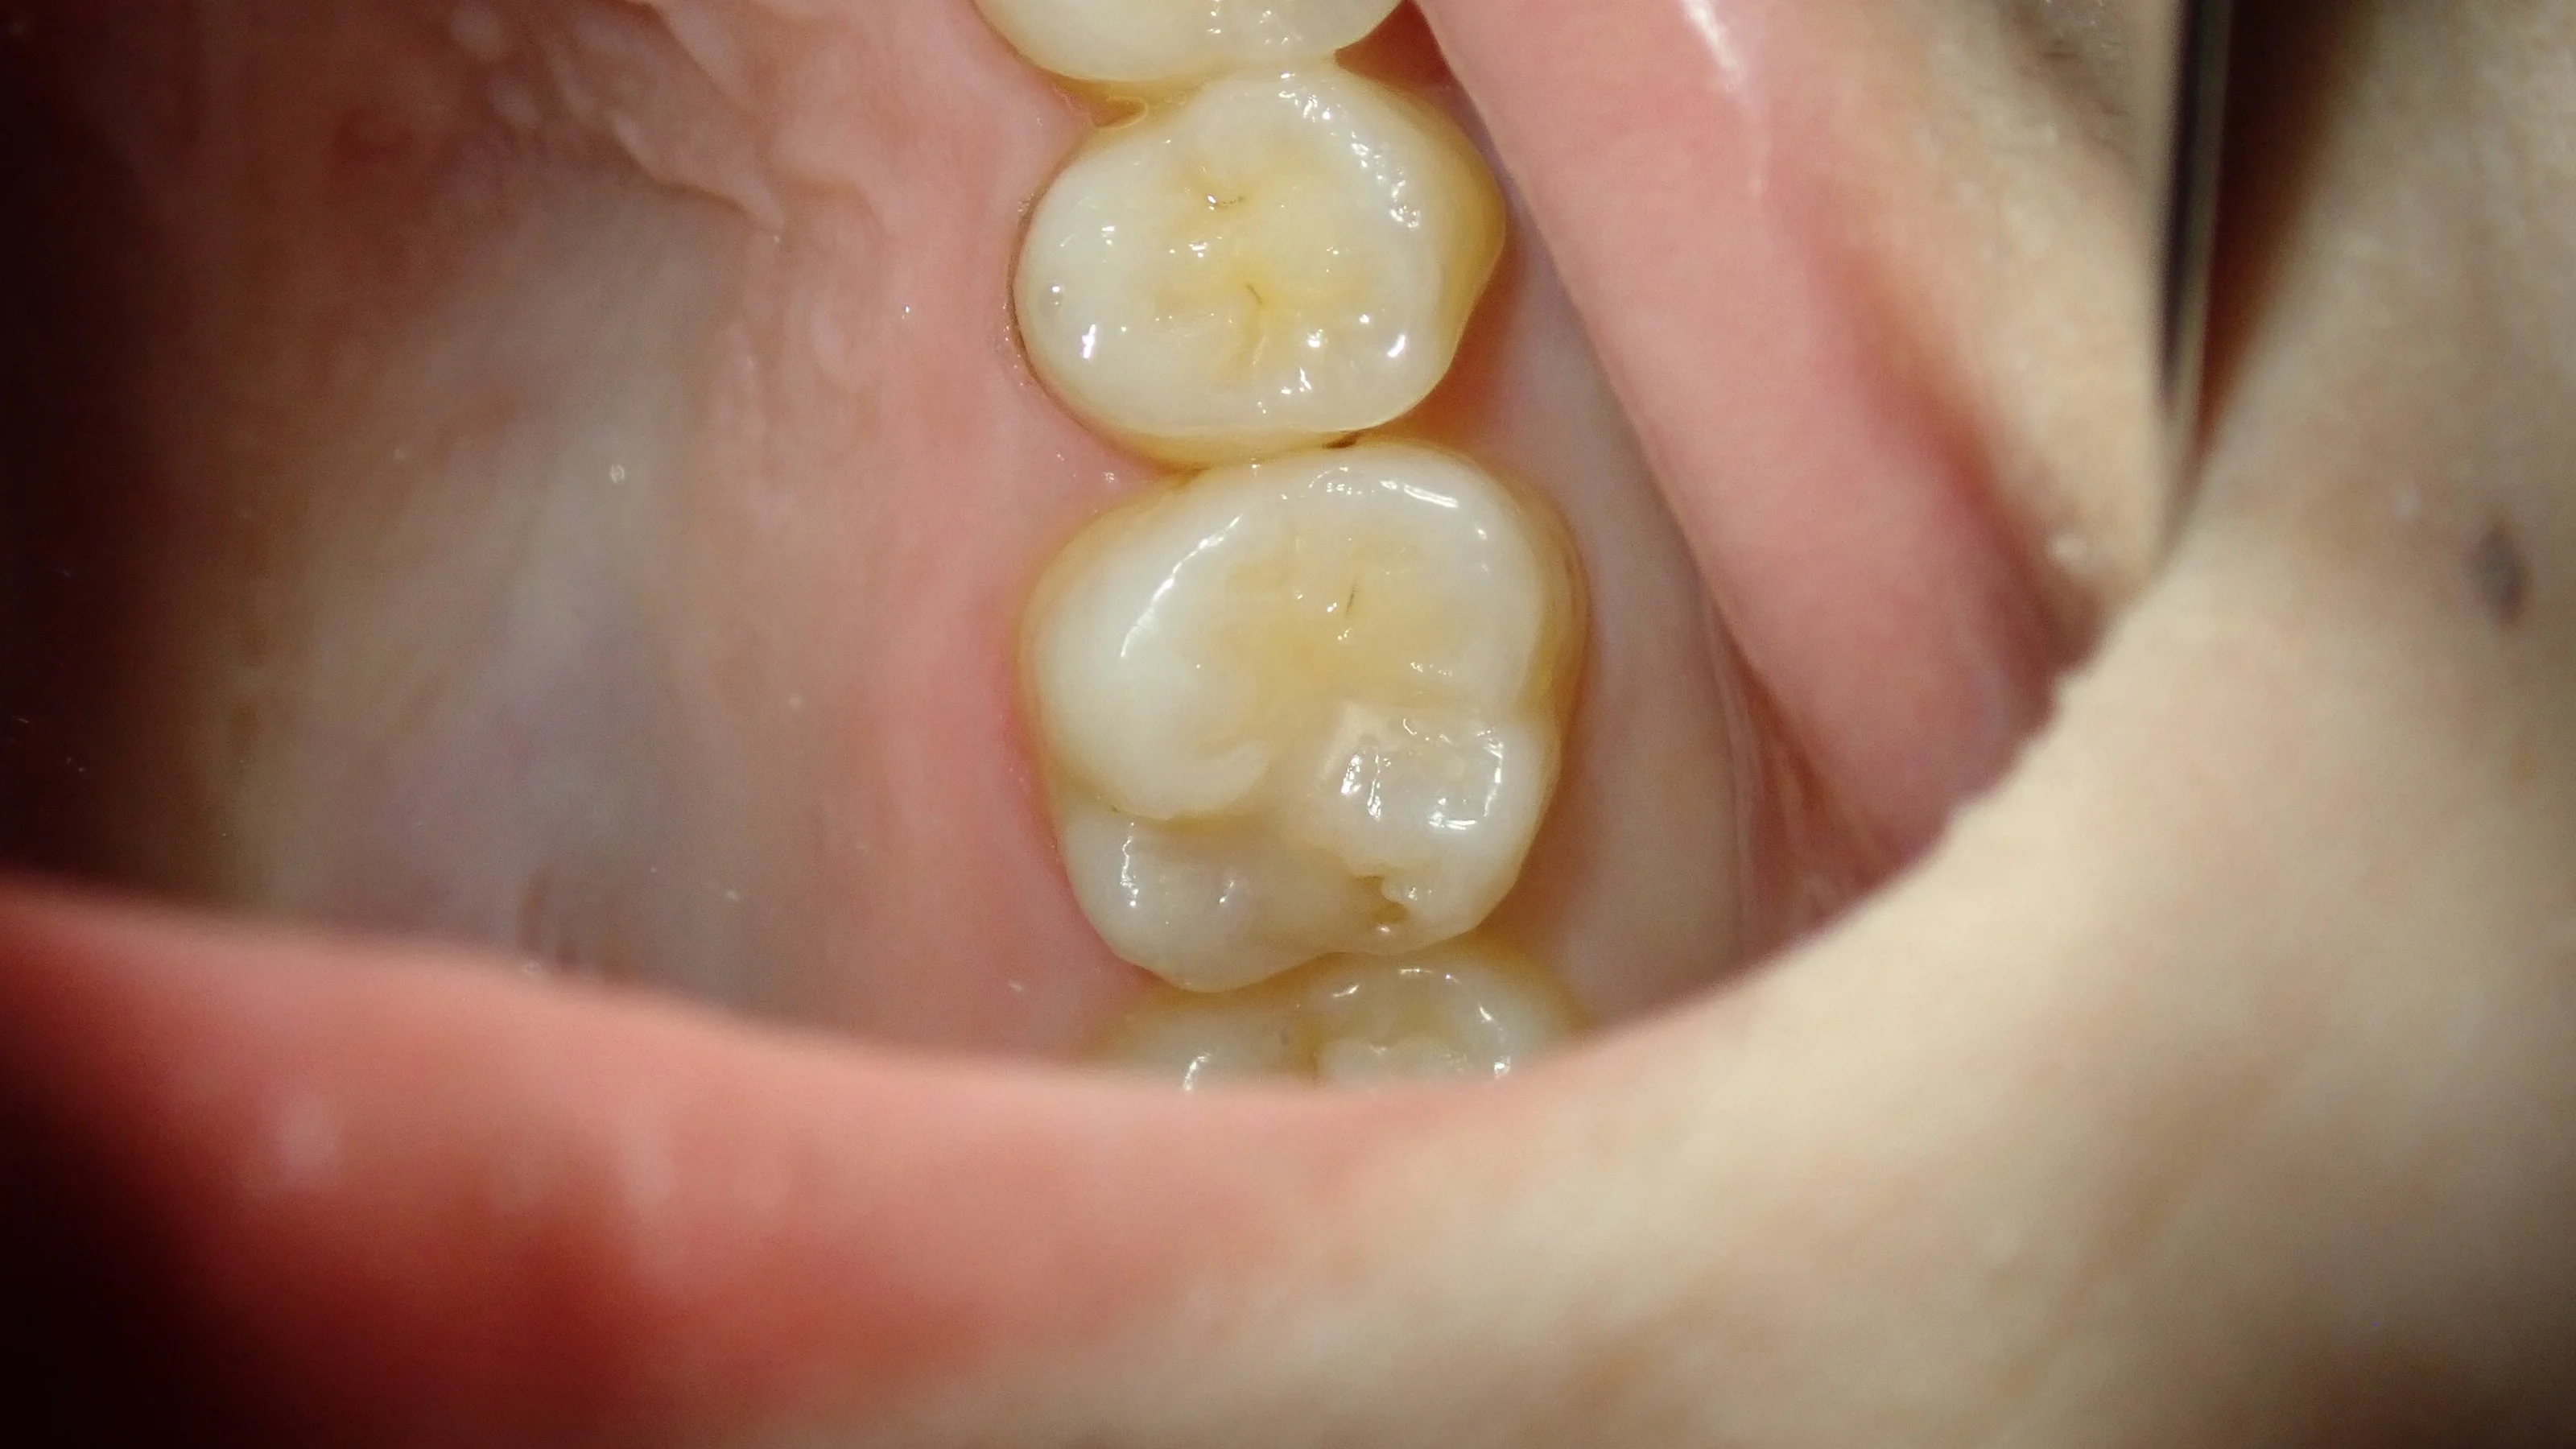

診た感じとしては特に問題なく、比較的真新しい詰め物が普通に詰められている状態でした。

レントゲン像としてはこんな感じです。

レジンを除去しきった状態ですが・・・

あからさまに穴が開いています。